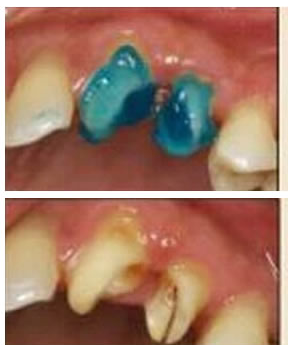

8.根管內(nèi)酸蝕劑的去除

使用全酸蝕粘結(jié)系統(tǒng)粘接纖維樁時,需要應用磷酸凝膠對根管進行酸蝕處理,然后再徹底沖洗干凈。根管內(nèi)酸蝕劑的殘留是臨床上經(jīng)常發(fā)生且容易被忽視的問題,也是影響纖維樁粘接的重要因素之一。單獨使用三用槍即使反復沖洗也很難將根管內(nèi)的酸蝕劑清除干凈,尤其是后牙根管。臨床建議應用注射器、三用槍和柱狀毛刷,三者聯(lián)合使用反復沖洗,以免酸蝕劑殘留于根管內(nèi)(圖 19-1至圖 19-4)。有條件者也可使用超聲波蕩洗根管。

圖19-1:冠部及根管全酸蝕。圖19-2:三用槍沖洗。圖19-3:注射器沖洗。 圖19-4:根管毛刷清洗。